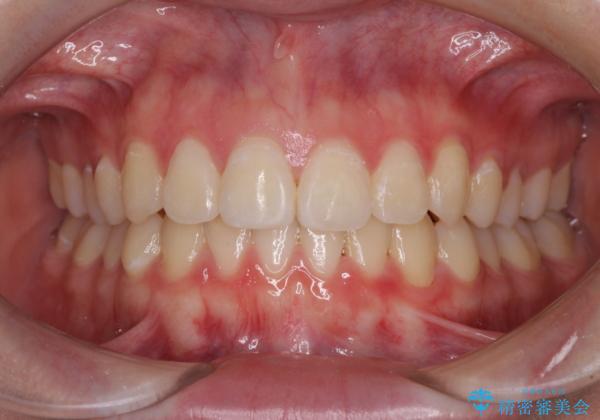

ゴムかけをしっかりと行ってもらい、スッキリとした口元に仕上げることができました。